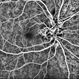

- pediatic retina, vascular anomaly

- Maria A. Martinez-Castellanos. Asociacion para Evitar la Ceguera en Mexico

- Imaging device

- RetCam II

- Fundus photograph of a 3-year-old boy with low vision, esotropia and leukocoria.